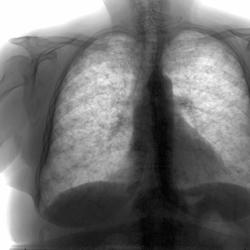

А вот и архив за февраль прошлого года, который просил Александр.

На архивном снимке справа медио-базально снижение прозрачности, которого видно поменее на "свеженьком" снимке...

Впрочем на "свеженьком" и корни слабовать видны из-за того, что "снежит"...